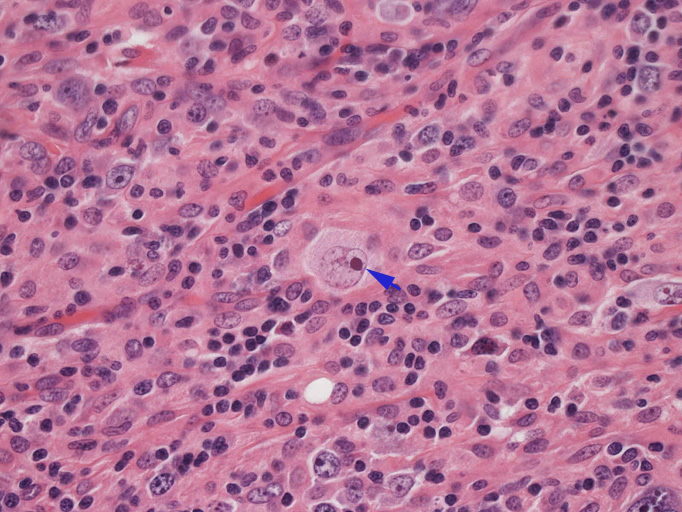

結節構造内では, 好酸性細胞質をもつ組織球の増生を背景に大型異型細胞が散在性または集蔟して増殖している。被膜下にも線維化組織内にbizzarreな大型細胞が認められる。リンパ球は小型リンパ球が大型異型細胞を含む組織球性の結節辺縁に存在する。大型細胞は, centroblastic cellが多く, その他 Hodgkin cell-like cell, RS細胞様巨細胞, 腎臓型の核をもった細胞, 多型核の細胞など多彩な形態を示す。異型核分裂像をふくむ核分裂像が多い。

- Hodgkin's cell, Reed-Sternberg細胞様大型細胞がしばしば認められる。

大型腫瘍細胞のシート状増殖はみられない。多彩な反応性背景をもちRS細胞様巨細胞が散在性に出現しホジキン病や反応性病変との鑑別が問題となる。